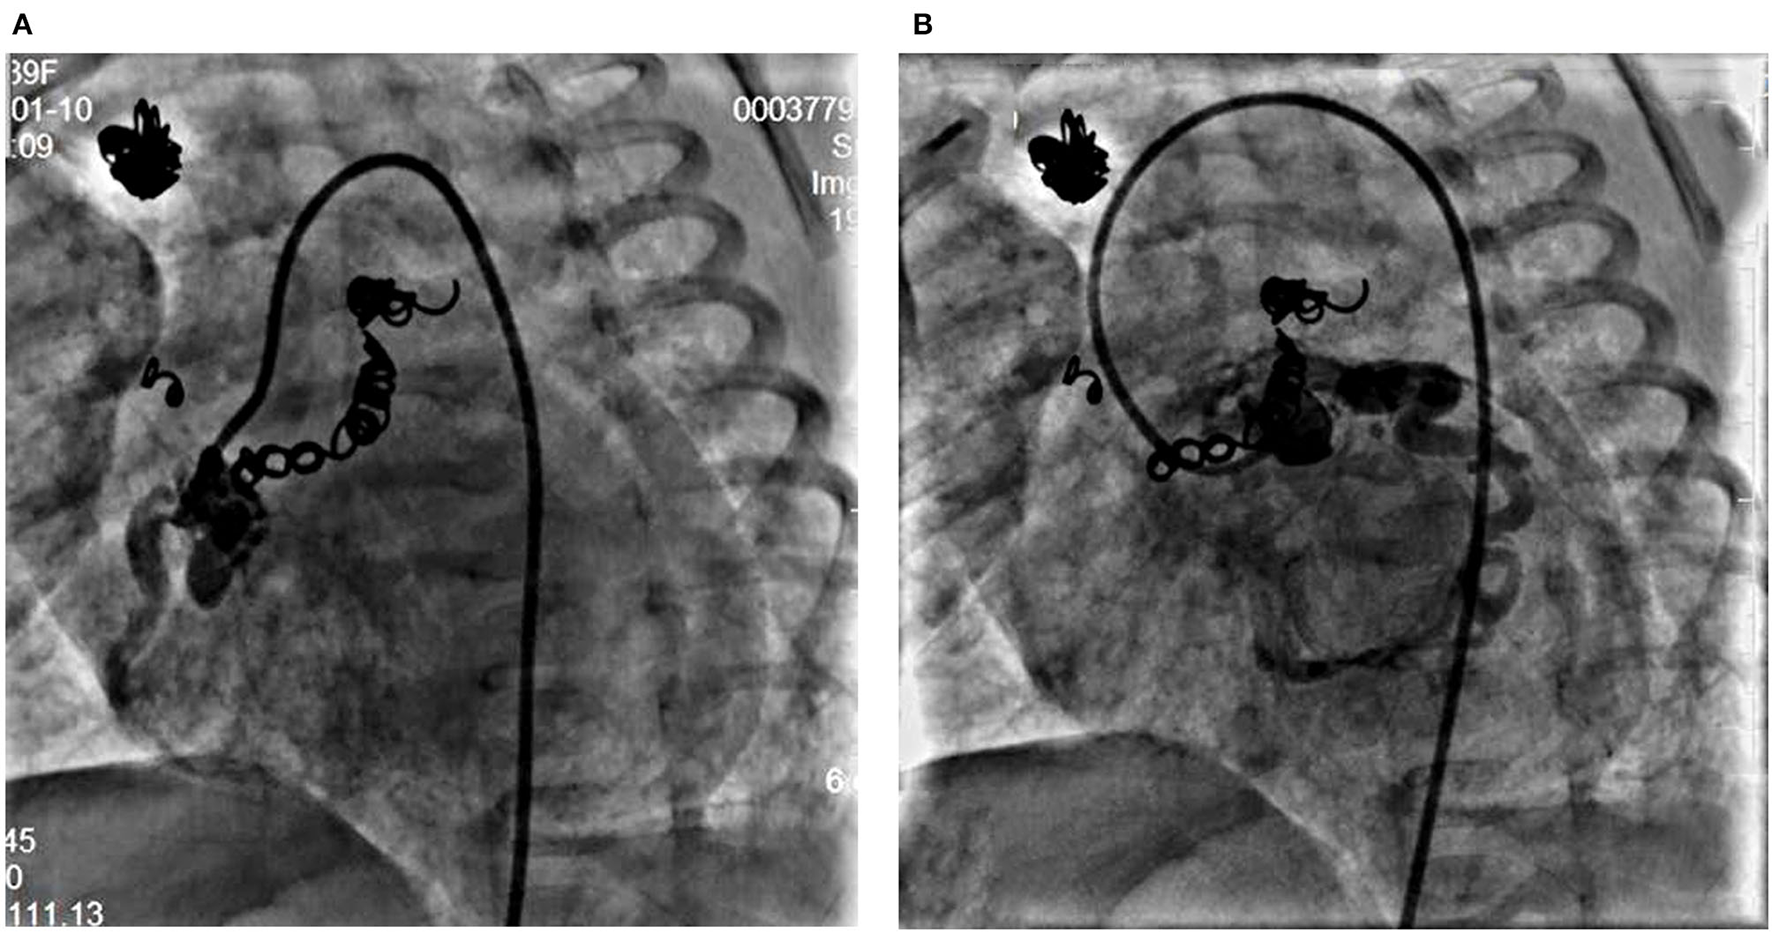

At the age of 5 weeks old, cardiac catheterization was performed for hemodynamic assessment and interventions. The pulmonary to systemic blood flow ratio was 4.29 with pulmonary vascular resistance 1.7 Wood unit *m2. A selective angiography revealed four collateral arteries draining into the right atrium. No. 1 (4.3 mm in diameter) of the collateral arteries was originating from the right subclavian artery (Figures 1A,C). No. 2 was seen at the level of the 6th thoracic vertebra and twisted to the right atrium (Figures 1B,D). No. 3 was a tortuous collateral artery (2.7 mm at the proximal and 1.7 mm at the minimal), located between the 6th and the 7th thoracic vertebra (Figures 1B,E). No. 4 was a very tortuous collateral artery between the descending aorta and the right atrium (Figures 1B,F). No. 1 and No. 3 collaterals were occluded with coils. Coronary arterial angiography also revealed a right coronary arterial fistula to the right ventricle and another to the right atrium (Figures 1A, 2A), and a fistula branching from the left anterior descending coronary artery to the right atrium (Figures 1A, 2B). Pulmonary arterial pressure was 43/22 mmHg.

Figure 2

Right coronary angiogram from left anterior oblique 45° view shows the dilated right coronary artery fistula with a proximal fistula to the right atrium and a distal fistula into the right ventricle (A). Left coronary angiogram shows a fistula from the left anterior descending coronary artery to the right atrium (B).